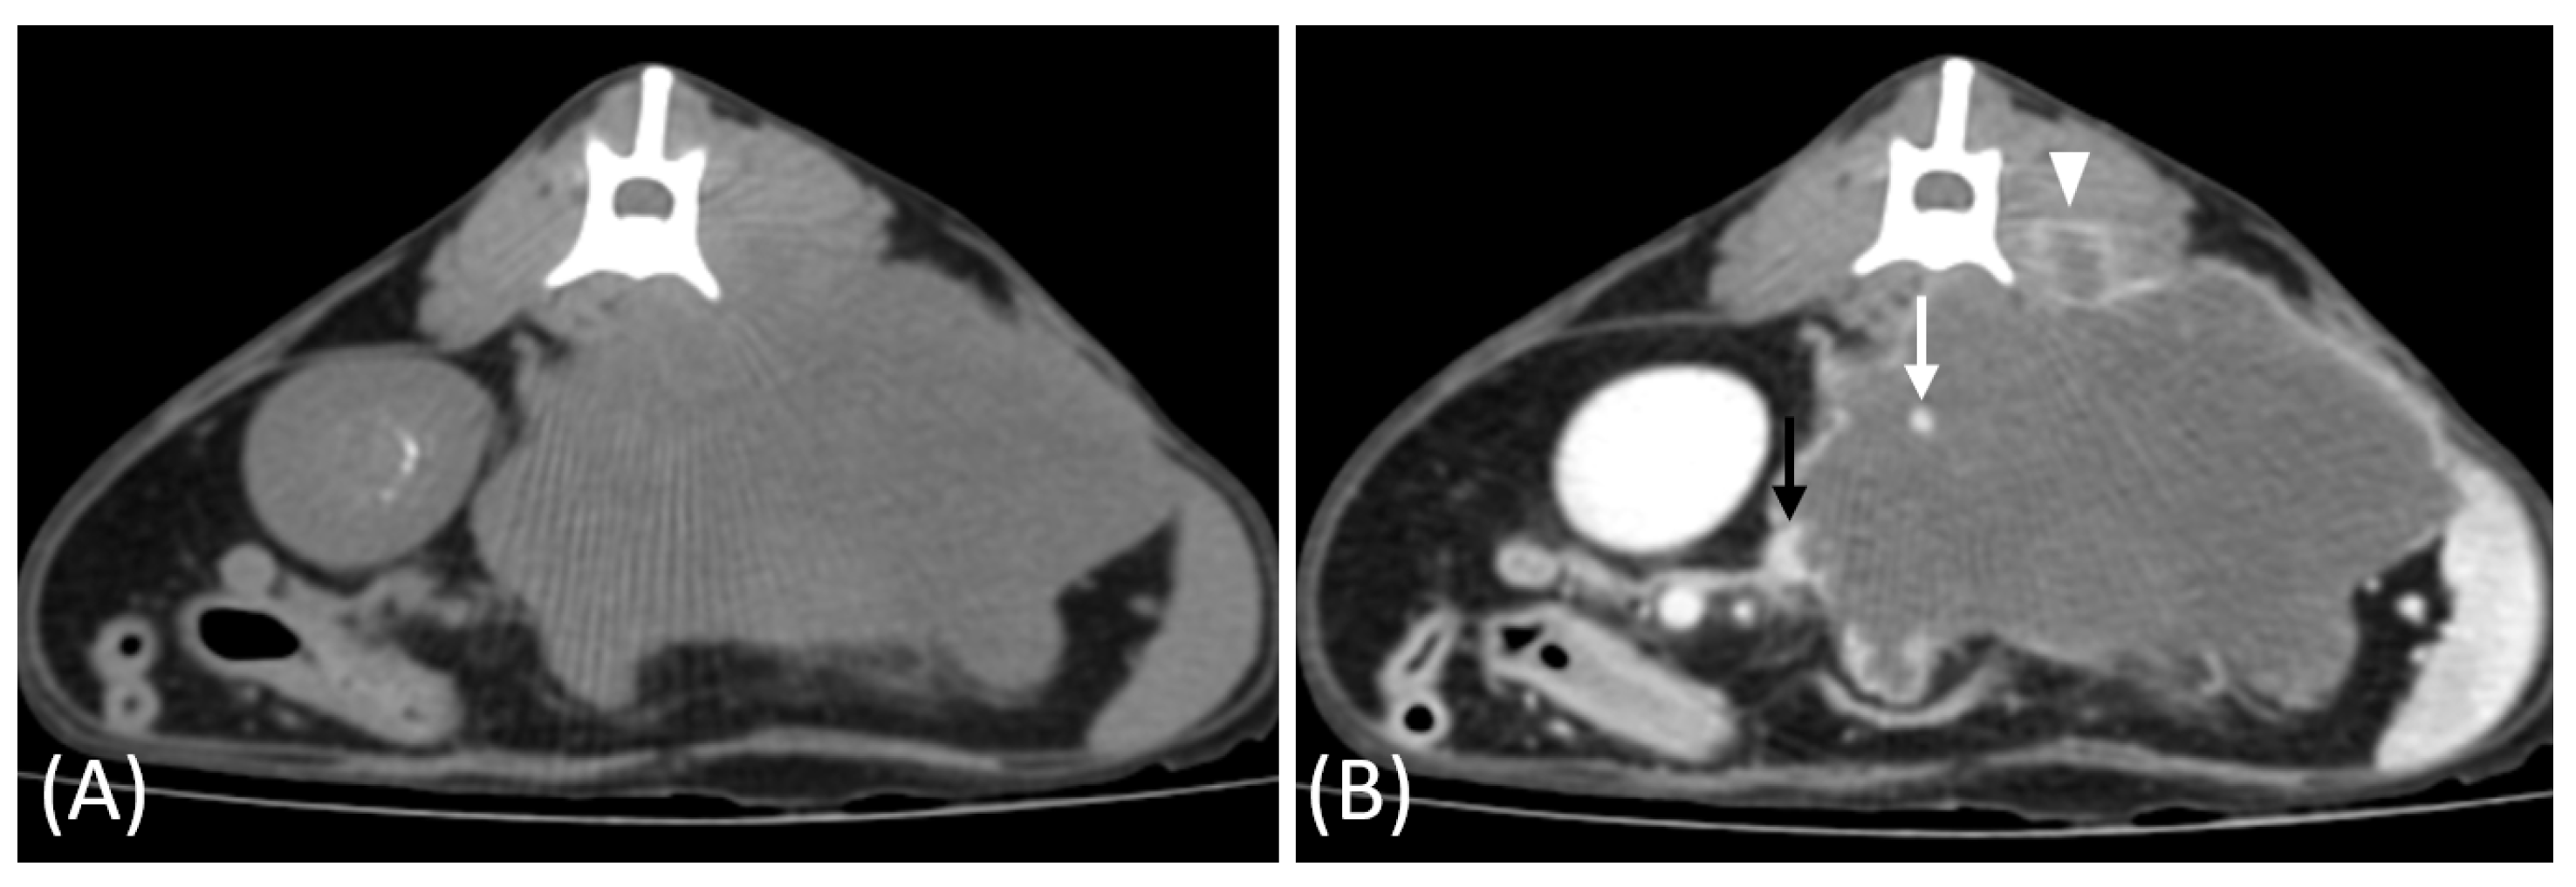

In the two cats that were excluded, the RCC tumors showed a distinct imaging pattern with rim enhancement but no internal enhancement on contrast-enhanced CT (Figure 7). The attenuation values of the tumors were approximately 23 HU and 33 HU across both the pre- and post-contrast phases.

Figure 7.

(A) Pre-contrast and (B) late nephrographic/early excretory phase contrast-enhanced computed tomography (CT) images of a renal cell carcinoma (RCC). The image shows a large renal mass with rim enhancement and no internal enhancement. Vascular structures such as the aorta (white arrow) and CVC (black arrow) are visible; however, the renal artery and vein are not clearly identifiable. Tumor invasion into adjacent musculature is observed (arrowhead).

Two RCC cases in this study exhibited a distinct imaging pattern characterized by rim enhancement without internal enhancement. This imaging feature likely reflects central necrosis or hypovascularity resulting from rapid tumor growth outpacing its blood supply. Additionally, one of the two cases demonstrated invasion into adjacent musculature, further supporting the aggressive nature of these tumors. While necrosis is a common cause of non-enhancement in tumors, other factors such as cystic changes, fibrosis, or hemorrhage may also contribute to this imaging feature [35]. Both cats succumbed to their disease within one month of diagnosis, suggesting the poor prognosis associated with this imaging pattern. Although histopathological confirmation was unavailable, these findings suggest the diagnostic value of imaging in characterizing aggressive tumors.